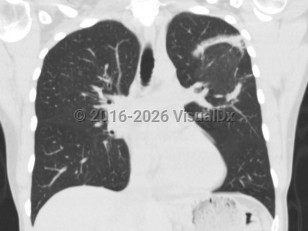

Cryptogenic organizing pneumonia

Patients typically present with relatively short duration of symptoms (weeks to months) including a persistent nonproductive cough, dyspnea, fever, malaise, weight loss, and occasionally other influenza-like symptoms (nasal congestion, headache, chills and sweats, sore throat, myalgia). Hemoptysis is uncommon. Physical examination reveals inspiratory crackles in a majority of patients, and radiographic findings include peripheral, patchy bilateral opacities.